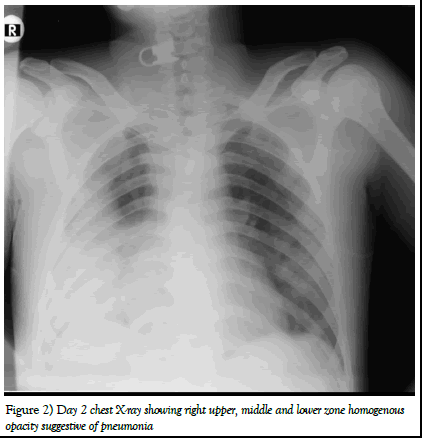

One day after admission he developed breathlessness and cough with expectoration. Later chest X-ray was done showing features of right upper, middle and lower lobe pneumonia [4].

Figure 2) Day 2 chest X-ray showing right upper, middle and lower zone homogenous opacity suggestive of pneumonia